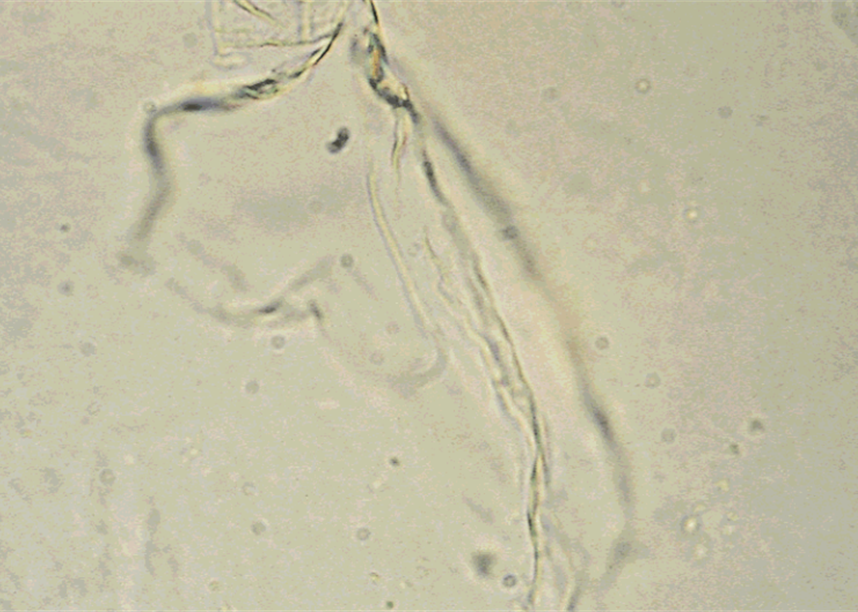

Mucus

LPF

Protein material made by the glands and epithelial cells